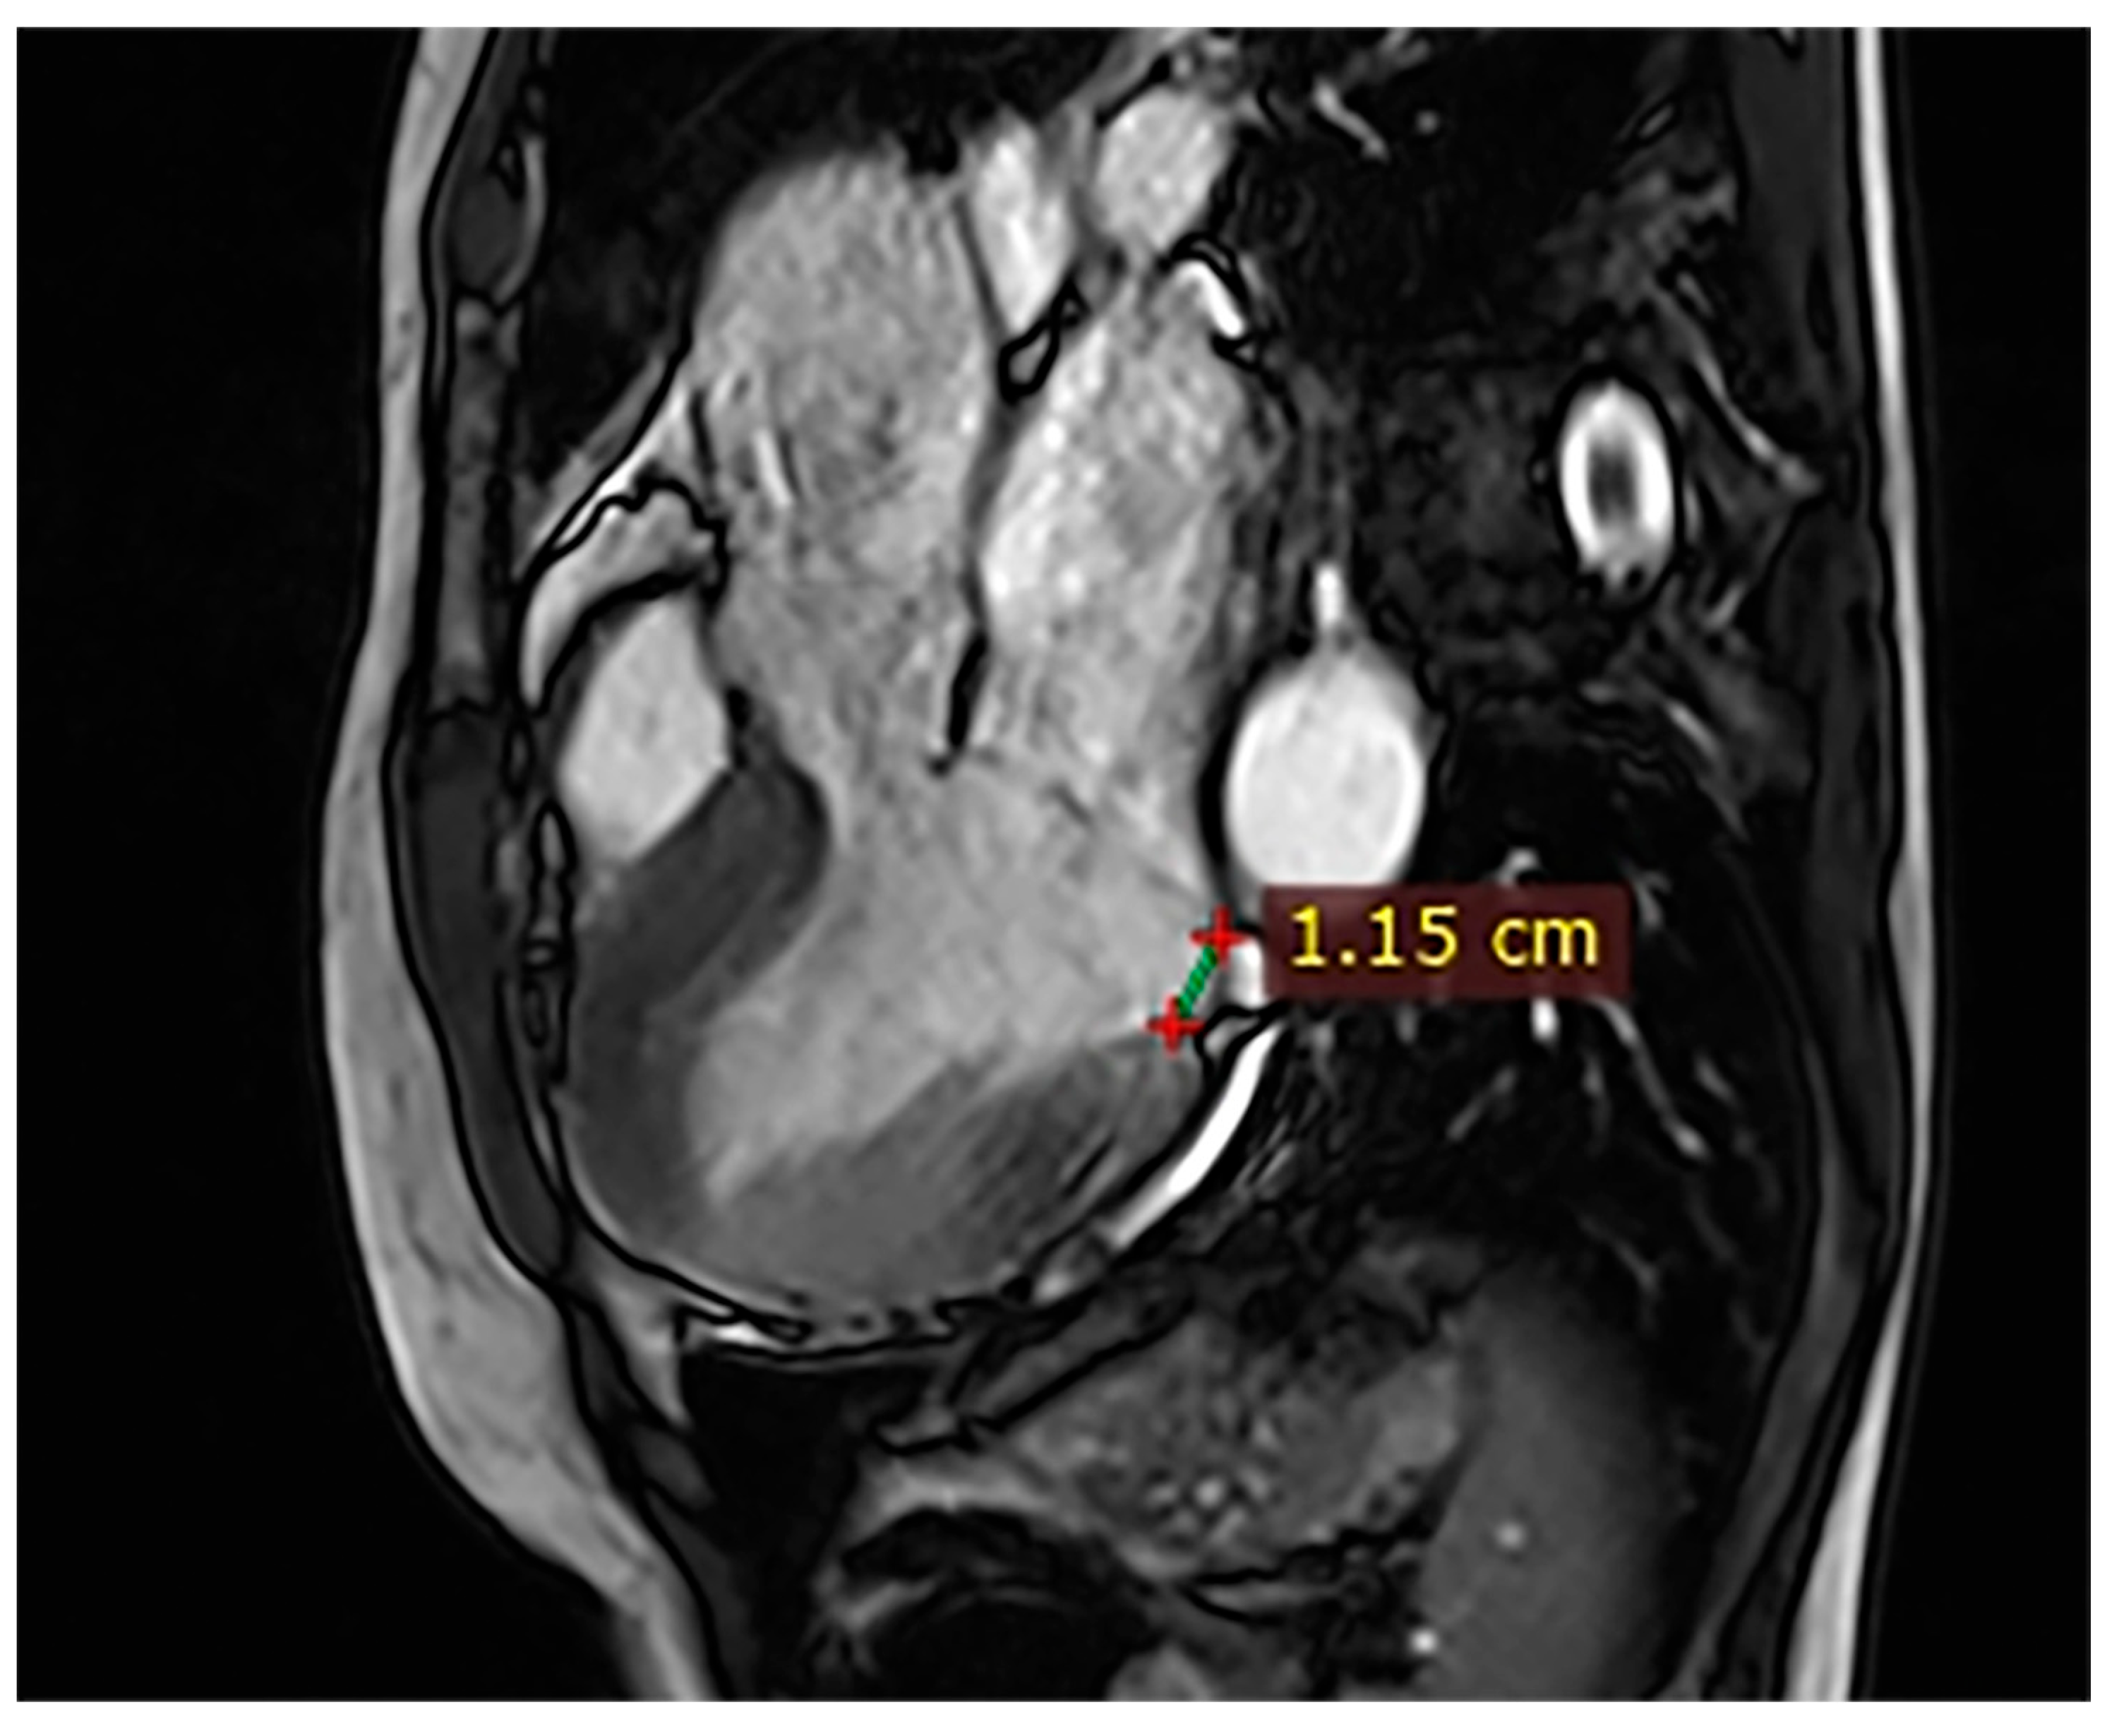

Case 4. A 34-year-old man with Marfan syndrome and premature ventricular contractions had CMR demonstrating preserved LVEF (54%), a posterior MAD of 15 mm (Figure 4), MVP with mitral regurgitation, and no LGE. Given the underlying connective tissue disease and valvular dysfunction, close cardiology monitoring was advised to evaluate progression and arrhythmic risk.

Figure 4.

Cardiac magnetic resonance (CMR), three-chamber steady-state free precession (SSFP) cine. A 15 mm mitral annular disjunction (MAD) with associated mitral valve prolapse (MVP) in a patient with Marfan syndrome is observed.